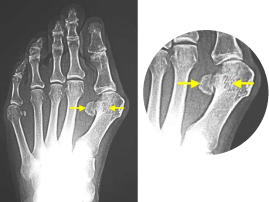

巻き爪、タコ、魚の目等があると症例に示すように、様々な症状を呈します。

早いうちに処置をして快適な生活を心がけましょう。